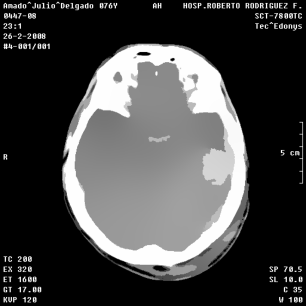

An example of an applications of our proposed strategy to a medical image is shown in Figure 7. In this case, we used different values of and in the . This is a preliminary result. A deeper paper about these results will be published.